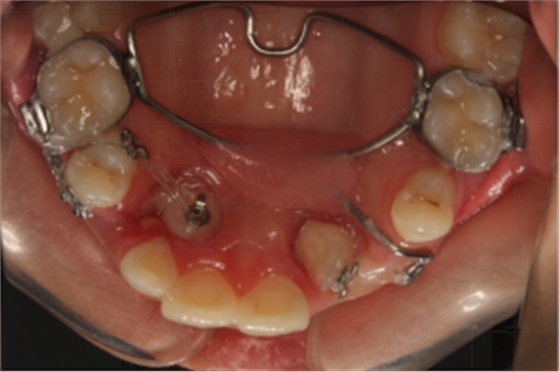

14:30-15:30 正畸患者的埋伏牙開窗術(shù)

【精彩病例】